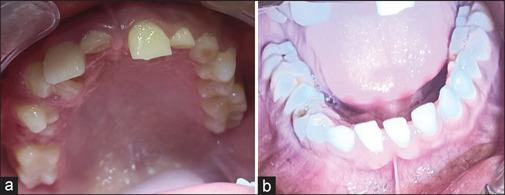

Keratocyst is a developmental odontogenic cyst arising from remnants/rests of the dental lamina with biologic behavior similar to benign neoplasm. The presence of multiple odontogenic keratocysts is rare and seen in Gorlin-Goltz syndrome (GGS). GGS syndrome presents with multisystem involvement and the classical triad of multiple basocellular epitheliomas, keratocysts in the jaws, and bifid ribs; that characterize the diagnosis of this syndrome. Multiple odontogenic keratocyst are the most consistent features of the syndrome in 65%-100% of affected individuals and are generally diagnosed at a very early age. Early diagnosis and proper counseling of the parent and patient might help to reduce the morbidity, encourage follow-up for timely treatment, and help in avoiding ionizing radiation that would lead to the development of malignancies.

牙源性角化囊肿是一种发育性牙源性囊肿,起源于牙板的残余/遗迹,其生物学行为类似于良性肿瘤。多发性牙源性角化囊肿罕见,见于戈林-戈尔茨综合征(GGS)。GGS综合征表现为多系统受累,具有多发性基底细胞上皮瘤、颌骨角化囊肿和肋骨分叉这一经典三联征,这些特征可用于该综合征的诊断。多发性牙源性角化囊肿是该综合征在65%-100%的受累个体中最一致的特征,通常在非常早的年龄被诊断出来。早期诊断并对家长和患者进行适当的咨询可能有助于降低发病率,鼓励进行随访以便及时治疗,并有助于避免导致恶性肿瘤发生的电离辐射。